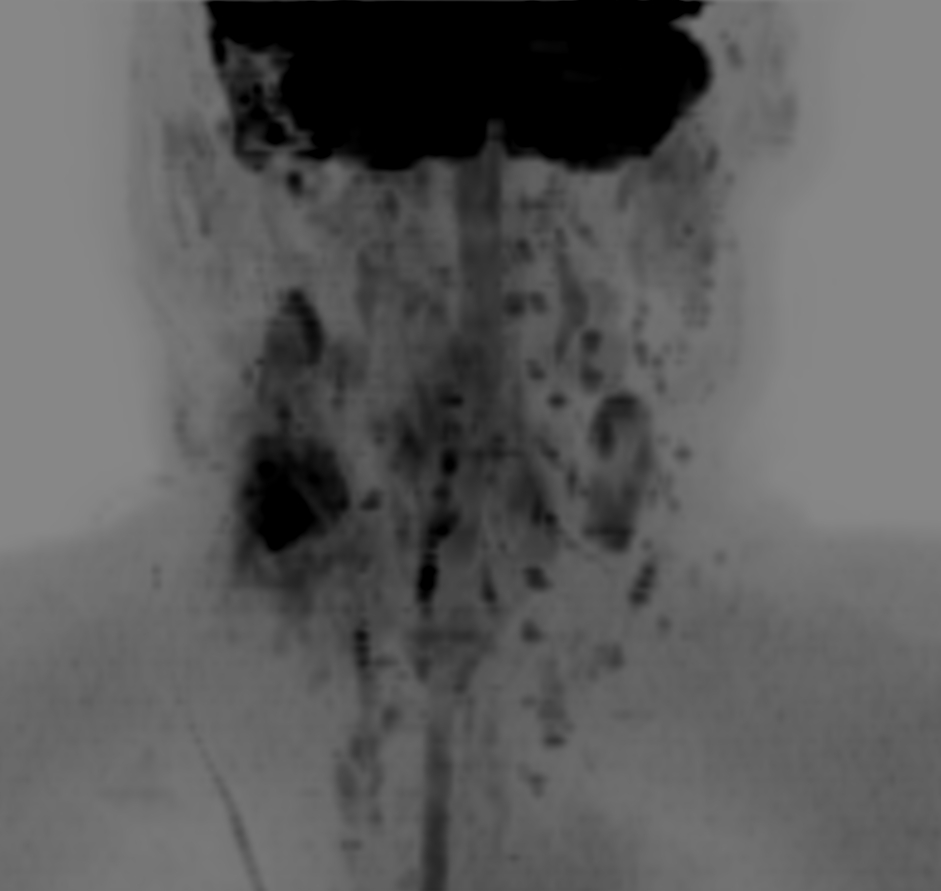

DWIBS (b700) - Coronal MIP